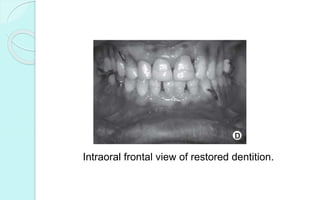

Intraoral frontal view of restored dentition.

Intraoral frontal viewof restored dentition.